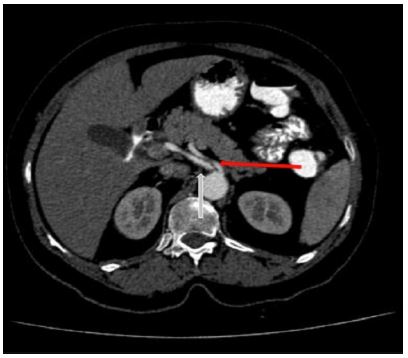

E.g., MALS i.e., Median arcuate ligament syndrome (Dunbar syndrome). The median arcuate ligament is a fibrous arch uniting the diaphragmatic crura at the level of the aortic hiatus and passes superior to the coeliac artery origin. However, if the insertion is low, it can cause abdominal pain. The diagnosis of coeliac axis compression / median arcuate ligament syndrome / Dunbar syndrome is done with conventional angiography/ CT angiography. The CECT imaging findings are characteristic focal narrowing in the proximal coeliac axis with a characteristic juxta-ostial hooked appearance with coeliac artery origin stenosis (Figure 7)[2].

Figure 7: Sagittal CT reformats showing juxta ostial fishhook configuration of the coeliac artery with narrowing of the coeliac artery near the origin (Red arrow).